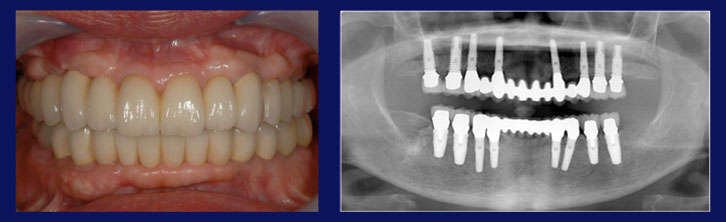

この方々は、毎日しっかり歯磨きをされていましたが、この写真ように多くの歯を失うことになりました。しっかりとケアしていたにも関わらず、なぜ歯を失うことになってしまったのでしょう?

その原因は、かみ合わせの悪さでした。

かみ合わせの悪さは、歯並びだけの問題ではなく、虫歯治療で入れたつめ物のバランスの悪さ、入れ歯の未使用といったものから、加齢による歯のすり減りなど、いくつかの原因によって引き起こされます。

かみ合わせが悪いと、一部の歯に大きな負担がかかります。噛むときに歯にかかる力は、成人男性の平均で約60kgと言われていますが、長年、その力を過剰に受け続けた歯は、その負担に耐えきれず、ある年齢に達したときにダメになってしまいます。

1本の歯がダメになると、周りの歯にもズレやゆがみなどの問題が広がり、かみ合わせの悪さがどんどん進行して、最終的にの画像のような状態まで悪化してしまいます。